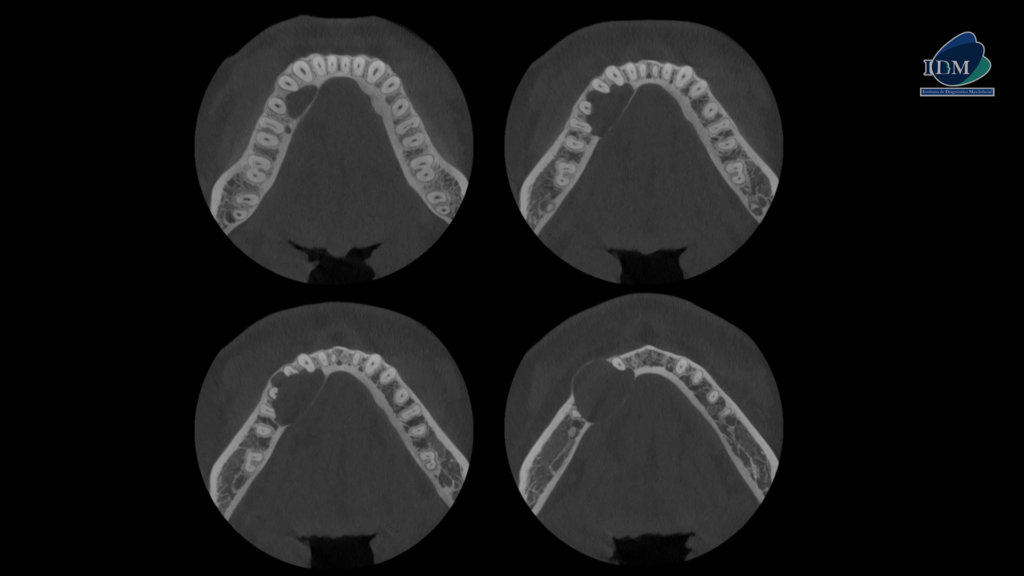

A la evaluación de la tomografía volumétrica (CBCT) en los cortes axiales (Figura 2) y transaxiales (Figura 3), se aprecia imagen isodensa unilocular que se extiende en sentido cefálico caudal desde cima del reborde alveolar hasta la cortical superior del conducto dentario inferior, en sentido mesio distal desde mesial de pieza 16 hasta

apical de pieza 13, que ocasiona borramiento parcial de la lámina dura de piezas 16, 15, 14 y 13, reabsorción radicular del tercio apical de pieza 14 y 15, borramiento parcial de la cortical superior del conducto dentario inferior y agujero mentoniano, adelgazamiento y expansión de tabla ósea vestibular; adelgazamiento, expansión y erosión de tabla ósea lingual. En las reconstrucciones 3D se representa de manera didáctica el compromiso que tiene la lesión con las estructuras adyacentes. (Figura 4).

CORTES AXIALES

CORTES TRANSAXIALES